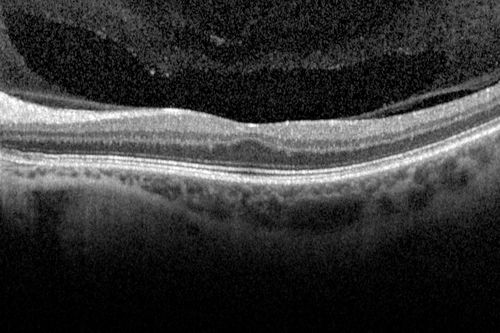

Foveal hypoplasia - aplasia

SD OCT shows persistent plexiform layers in the center of the macula